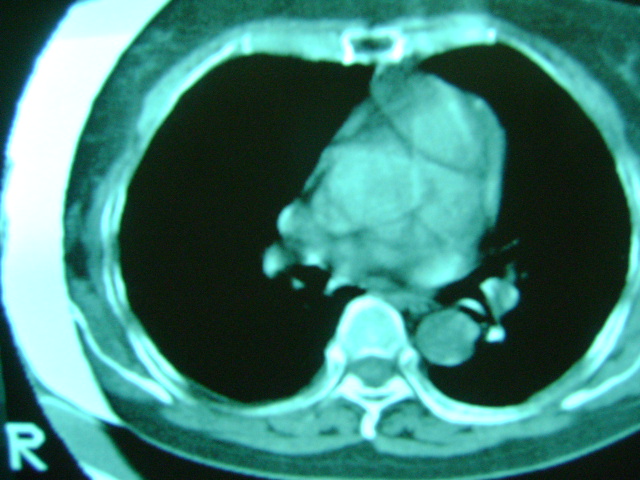

朋友的母亲,56y,咳嗽三个月,感觉左肺门不对,请大家给点意见

左肺门未见异常‘右肺有少许感染,图象质量不好